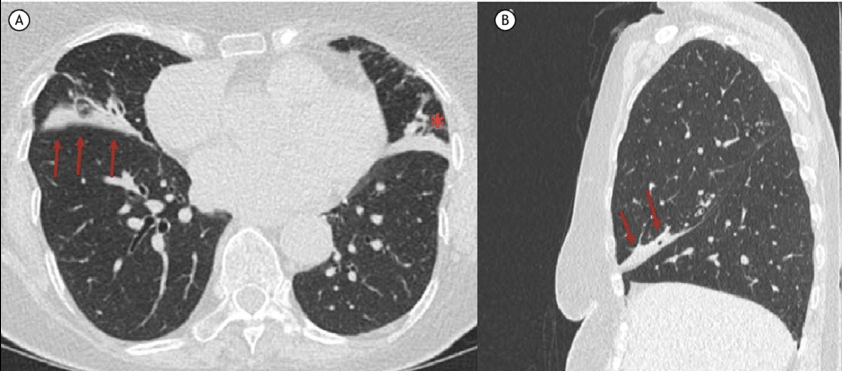

Atelectasis를 CT에서 구분하는 가장 중요한 단서는 폐 용적의 감소이다.

이를 volume loss라고 부른다.

폐렴이나 ARDS에서는 폐 용적이 크게 줄어들지 않는 경우가 많지만

atelectasis에서는 폐가 실제로 작아지기 때문에 주변 구조물이 함께 이동한다.

CT에서 확인할 수 있는 대표적인 volume loss 소견에는 여러 가지가 있다.

첫째, 폐엽 사이의 fissure가 이동한다.

폐가 줄어들면 인접한 폐엽 경계가 당겨지면서 fissure 위치가 변한다.

둘째, 횡격막이 상승한다.

폐가 허탈되면 횡격막이 위쪽으로 올라가는 모습이 나타날 수 있다.

셋째, 종격동 구조물이 병변 쪽으로 이동할 수 있다.

넷째, 폐 음영이 삼각형 또는 쐐기 모양으로 보이는 경우가 많다.